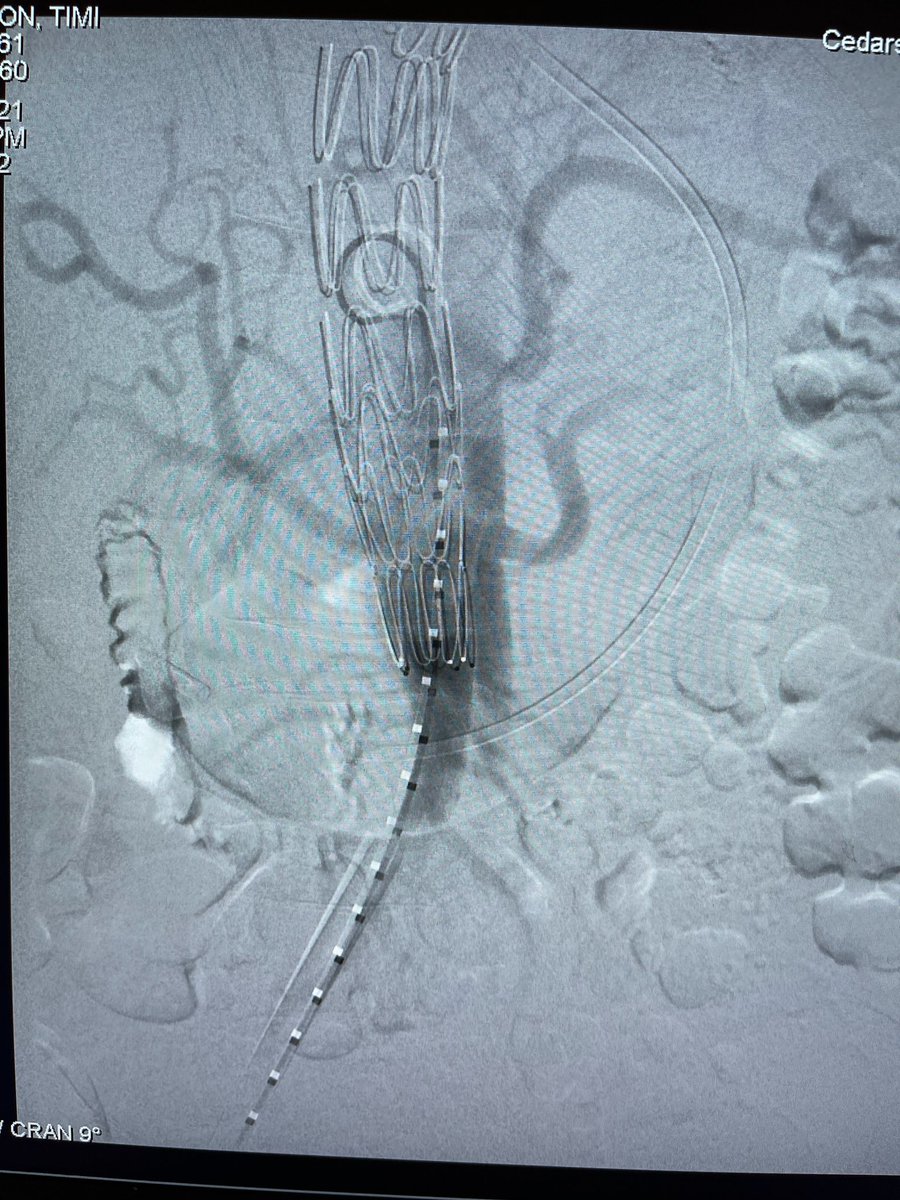

Great break from the SVS Moore Course: symptomatic TBAD with high-risk features = TEVAR + right RA stent and excellent result! Rameen S. Moridzadeh, MD Cedars-Sinai Division of Vascular Surgery Vascular Surgery Associates Department of Surgery at Cedars-Sinai Cedars-Sinai #AorticDissection #vascularsurgery